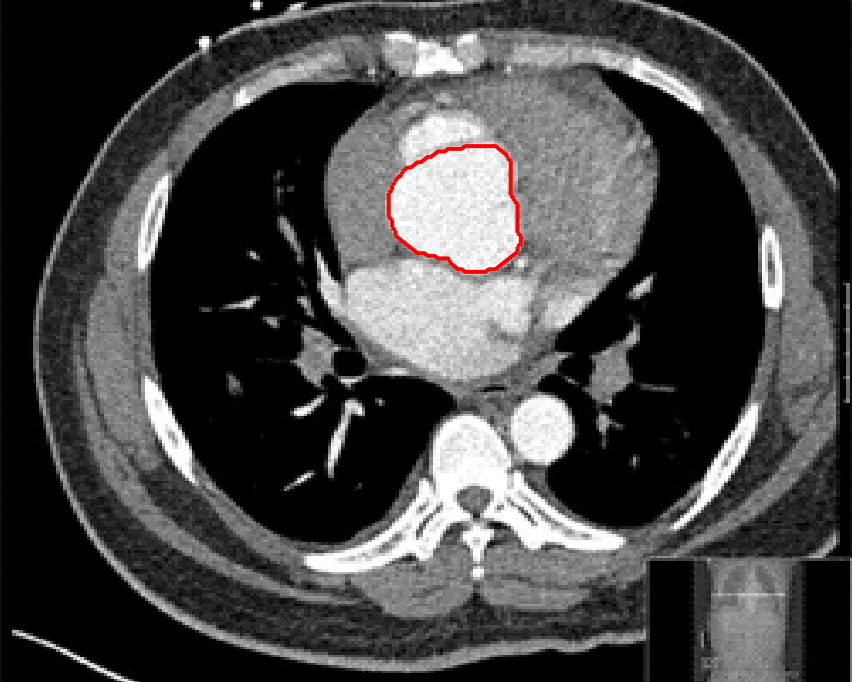

Refer to captionRefer to captionRefer to captionRefer to caption

(i)                                 (ii)                                 (iii)                                 (iv)

Figure 9: Test 1 setting: (i) Image 1;  (ii) Image 1 with marker and anti-marker set shown in green and pink respectively;  (iii) Test Image 2; (iv) Image 2 with marker set shown.

(g) M7 λ=10,θ=1formulae-sequence𝜆10𝜃1\lambda=10,\theta=1.

Figure 10: Visual comparison of M1 – M7 results for Test Image 1. M1 segmented part of the object, M2 – M4 failed to segment the object, M5 gave a reasonable result (though not accurate) and, M6 and M7 correctly segmented the object.